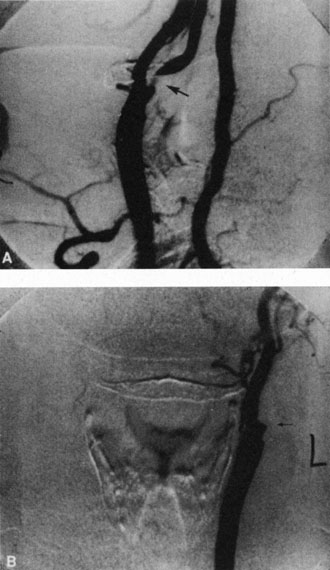

Hypoperfusion retinopathy is characterized by dot and blot hemorrhages in the midperiphery of the fundus, by venous tortuosity and engorgement, by microaneurysms, and by the occasional sludging of blood within the veins. Fluorescein angiography may show areas of capillary nonperfusion; it may also show microaneurysms in the midperiphery and slow arm to retina or arteriovenous transit time (Fig. 9A and 9B).174 The condition does not usually affect the posterior pole, and patients typically have normal visual acuity, although an occasional patient may have macular edema.174 The entire periphery of the eye is usually affected, although there may be more hemorrhages in one quadrant than another. Patients occasionally experience ocular discomfort or eye pain despite normal intraocular pressure. Reduction of the ophthalmic arterial pressure is a pathognomonic feature. Disc edema and disc collaterals are generally not present. The electroretinogram shows abnormalities in both the a- and b-waves (see Fig. 9C).

Fig. 9. Intravenous fluorescein angiogram of a patient with hypotensive or hypoperfusion retinopathy. A: There is a marked delay in the choroidal and retinal filling. B: In the recirculation of the angiogram, there is a characteristic staining of both arteries and veins. C: Electroretinogram shows normal a- and b-waves in the normal right eye (upper tracing) and marked redirection of the a- and b-waves in the affected left eye (lower tracing).

Histopathologic examination of eyes with hypotensive retinopathy demonstrates intraretinal hemorrhages and numerous microaneurysms, particularly in the midperiphery and periphery, and a decrease of the pericyte to endothelial cell ratio.175 The ophthalmoscopic appearance and effect on the retina and optic nerve has been reproduced in an animal model using mature rats after carotid artery ligation176,177,447–451. Unilateral carotid artery ligation has produced inconsistent and less severe changes.176 Symptoms do not occur until the blood flow in the carotid artery distal to a stenosis is reduced, which is only when the stenosis is more than 60% to 65%.177